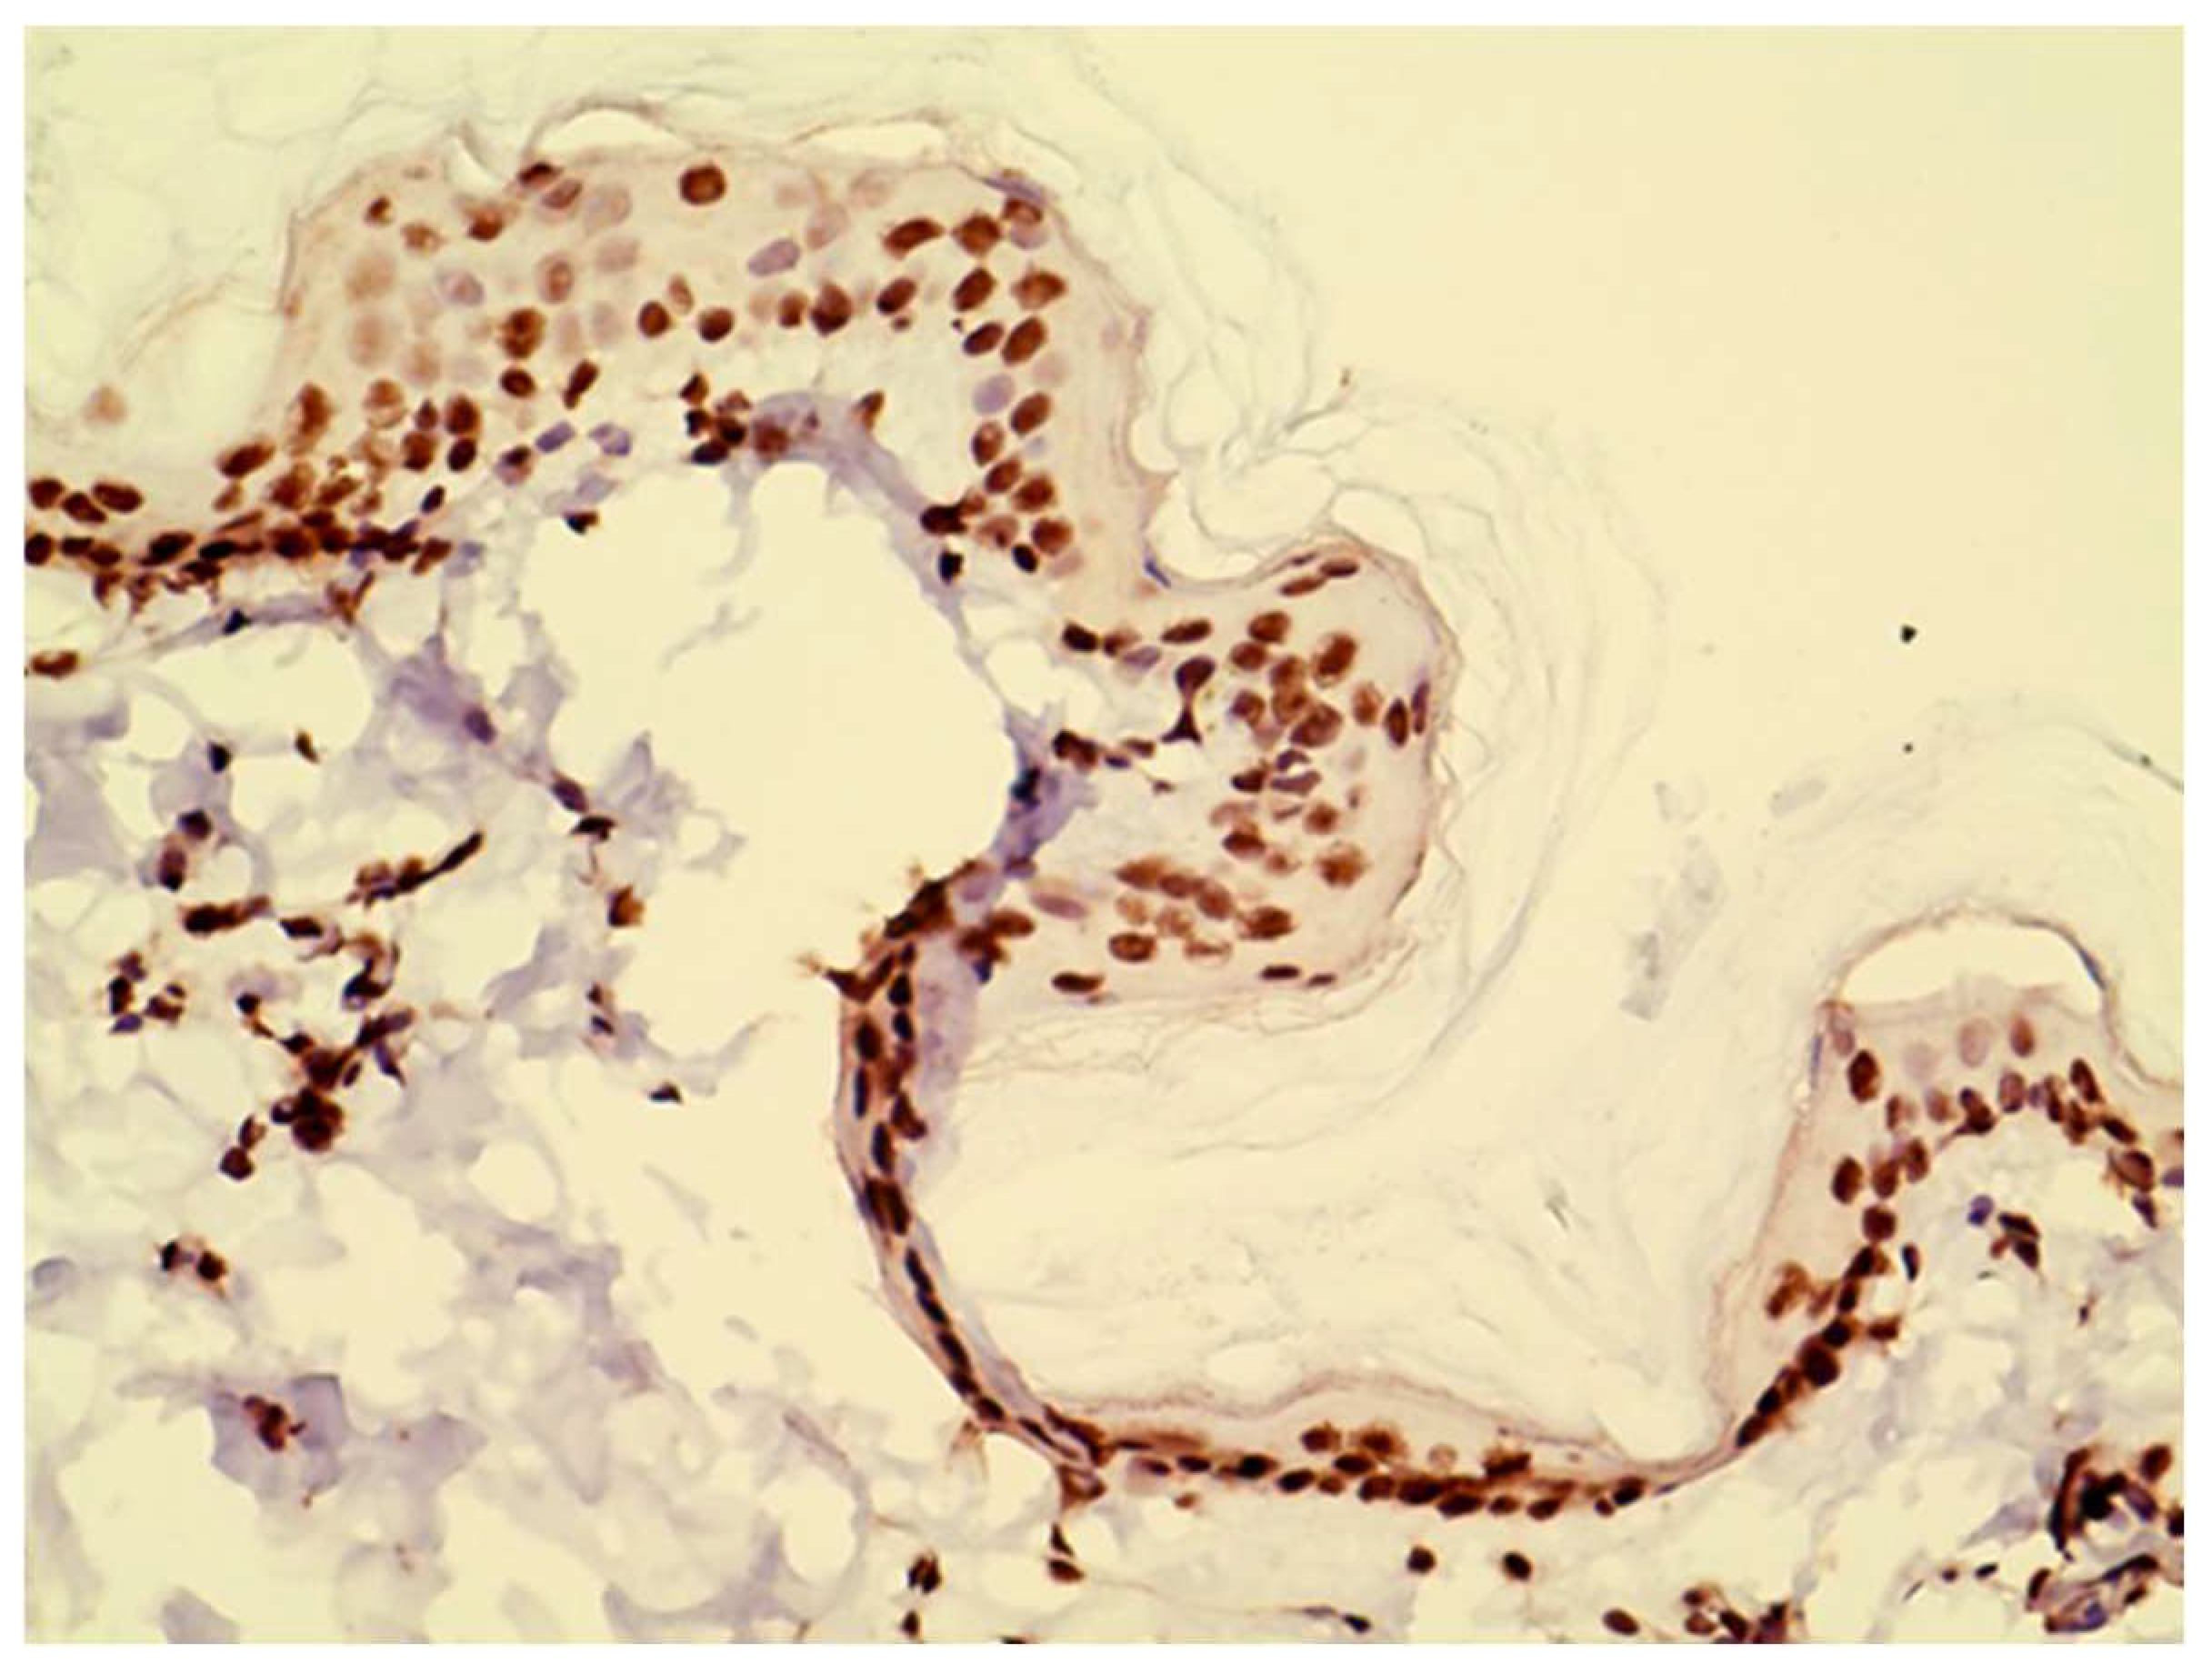

JAK1 and JAK3 staining was detected in both epidermis and dermis. JAK1 staining was cytoplasmic and primarily seen in basal keratinocytes and on dendritic cells (Figure 1). JAK3 was nuclear at all levels of the epidermis and on inflammatory cells in the dermis. (Figure 2 and Figure 3).

Figure 2. Example of JAK3 staining, which was nuclear at all levels of the epidermis and on inflammatory cells in the dermis.